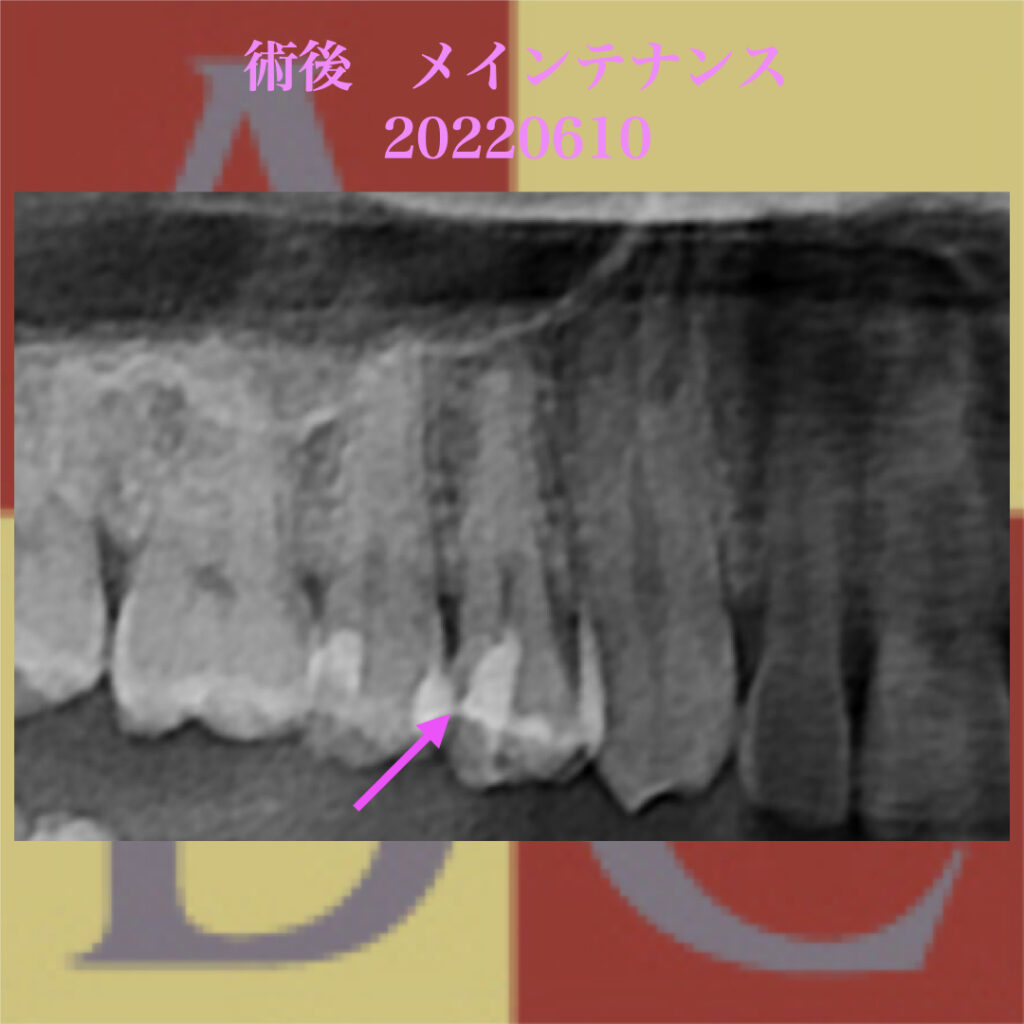

デンタルX線で確認すると、ダイレクトボンディング(DB)部分の境目の適合は良好。

歯髄直上にMTAセメント(赤い点線で囲まれた部分)が確認できる。

4時間で硬化するため、後日 接着修復を行った。

1年後のメインテナンス中のパノラマX線写真

歯髄に達するMTAセメントが確認できるが、

歯根膜腔の連続性を確認し、壊死後に現れる歯根膜腔の拡大が見られない。